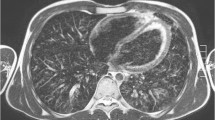

We selected only the right lung for the histogram analysis. We assessed all controls and two children with cystic fibrosis with prominent mucus plugging and wall thickening. Only the aggravated cases were taken into consideration because mild cystic fibrosis cases didn’t present large pixel distribution changes to the controls. Figure 6 shows a representative axial slice of the segmented lung of a control subject and of both children with cystic fibrosis. All histograms were positively skewed. The average skewness among all controls was 1.75; for the child with cystic fibrosis and mucus plugging, 0.87; and for the child with wall thickening, 1.90; the kurtosis values were 1.6, 0.5 and 4.4, respectively.

Axial slices at carina level of a 5-month-old male control scanned with (a) cones and (b) fast spin echo. Cones provides higher contrast inside the lungs compared to the background and the signal of the trachea, which indicates capture of the lung parenchyma. Fast spin echo does not show any higher lung contrast. Qualitatively, cones delivers the highest lung contrast for newborns, compared to older patients (shown in Figs. 8 and 9)

Axial slices at the carina level of a 31-month-old girl control subject scanned with (a) cones and (b) fast spin-echo sequence. Cones provides higher contrast inside the lungs compared to the background and the signal of the trachea, which indicates capture of lung parenchyma. Fast spin-echo sequence does not show any higher lung contrast

Axial slices at carina level of an 18-year-old female control subject scanned with (a) cones and (b) fast spin echo sequence. Using cones provides higher contrast inside the lungs compared to the background and the signal of the trachea, which indicates capture of lung parenchyma. Fast spin echo does not show any higher lung contrast. Compared to the younger patients (shown in Figs. 7 and 8), cones provides the smallest lung contrast that is associated with lower lung signal intensity with increasing age